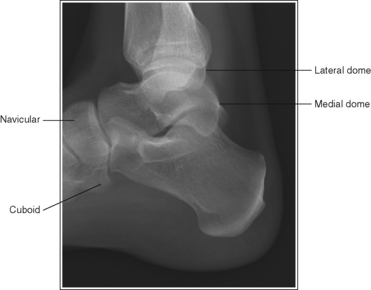

The foot is in a lateral projection. The talar domes are superimposed, the tibiotalar joint is open, and the distal fibula is superimposed by the posterior half of the distal tibia.

The height of the longitudinal arch can be determined by measuring the amount of cuboid demonstrated posterior to the navicular bone. The average lateral foot projection demonstrates approximately 0.5 inch (1.25 cm) of the cuboid, as shown in Figure 6-23. Because the bones that form the foot arch are held in position by ligaments and tendons, weakening of these tissues may result in a decreased or low arch. On a lateral foot projection, this decrease in arch height is demonstrated as a decrease in the amount of cuboid demonstrated posterior to the navicular bone. Figure 6-20 shows a lateral foot projection of a patient with a low longitudinal arch and approximately 0.25 inch (0.6 cm) of cuboid posterior to the navicular bone, whereas Figure 6-22 shows a patient with a high arch and approximately 0.75 inch (2 cm) of cuboid posterior to the navicular bone.

• Talar domes. The domes of the talus are formed by the most medial and lateral aspects of the talar's trochlear surface. On a lateral foot projection, they appear as domed structures that articulate with the tibia. On a properly positioned lateral foot projection, the talar domes should be superimposed and appear as one and the tibiotalar joint should be open. When the lateral foot is mispositioned, the domes are individually demonstrated, and they obscure the tibiotalar joint. Proximal-distal misalignment of the domes results from poor knee and lower leg positioning, and AP misalignment of the domes results from poor foot positioning.

When viewing a lateral foot projection that demonstrates one of the talar domes proximal to the other, evaluate the height of the longitudinal arch and the degree of narrowing or widening of the talocalcaneal joint to determine which dome is the proximal dome. If the navicular bone is superimposed over more of the cuboid than expected and the talocalcaneal joint is narrowed, the lateral dome is the proximal dome; if the navicular bone is superimposed over less of the cuboid than expected and the talocalcaneal joint is wider, the medial dome is the proximal dome.

• Effect of foot positioning on AP talar dome superimposition. To demonstrate accurate AP alignment of the talar domes, position the lateral surface of the foot parallel with the IR. If this surface is not parallel with the IR, one of the talar domes is demonstrated anterior to the other. When the leg is rotated more than needed to place the lateral foot surface parallel with the IR, as shown in Figure 6-29, the medial talar dome is demonstrated anterior to the lateral talar dome (see Image 20). If the leg is not rotated enough to place the lateral foot surface parallel with the IR, as shown in Figure 6-30, the medial talar dome is demonstrated posterior to the lateral talar dome (see Image 21).

When viewing a lateral foot projection that demonstrates one of the talar domes anterior to the other, evaluate the position of the fibula in relation to the tibia to determine how to reposition the patient. On most lateral foot projections with accurate positioning, the fibula is positioned in the posterior half of the tibia. If the fibula is demonstrated more posteriorly than this relationship on a lateral foot projection with poor positioning, the medial talar dome is anterior and the patient was positioned with the forefoot depressed and the heel elevated (leg externally rotated), as shown in Figure 6-29. If the fibula is demonstrated more anteriorly than this relationship, the medial talar dome is posterior and the patient was positioned with the forefoot elevated and the heel depressed (leg internal rotation), as shown in Figure 6-30.

The proximal metatarsals are at the center of the exposure field. The phalanges, metatarsals, tarsals, talus, calcaneus, 1 inch (2.5 cm) of the distal lower leg, and surrounding foot soft tissue are included within the collimated field.

• Centering a perpendicular central ray halfway between the distal toes and heel and the AP aspect of the foot places the bases of the metatarsals at the center of the exposure field.

• Open the longitudinal collimation enough to include the patient's toes and heel. Transverse collimation should be to a point 1 inch (2.5 cm) proximal to the medial malleolus (Figure 6-31).